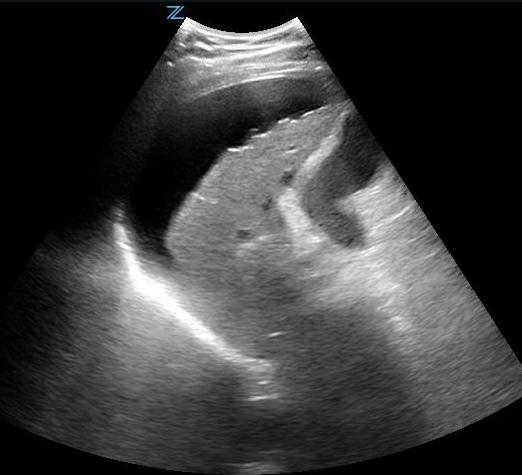

- Left Coronal and Intercostal Oblique Views:

- This is often the most difficult abdominal view to obtain. Place the probe in the posterior-axillary line at about the 6th to 9th intercostal space with the transducer indicator pointed cephalad, producing a coronal view. From this position the interface between the spleen and left kidney can be found.

- Free fluid is rarely seen between the spleen and the kidney but rather surrounding all other parts of the spleen or between spleen and diaphragm.

- To get rid of rib shadows, and to get a better view of the spleen, slide the probe cephalad and rotate it very slightly clockwise with the indicator pointing toward the posterior axilla, producing an intercostal oblique view, so that the spleen (not the kidney) is seen (Figure 13 shows the probe position). This view will allow good images of the lower tip and superior surface of the spleen, where intraperitoneal free fluid is most likely to collect. The diaphragm will also be seen in this view, just superior to the spleen.